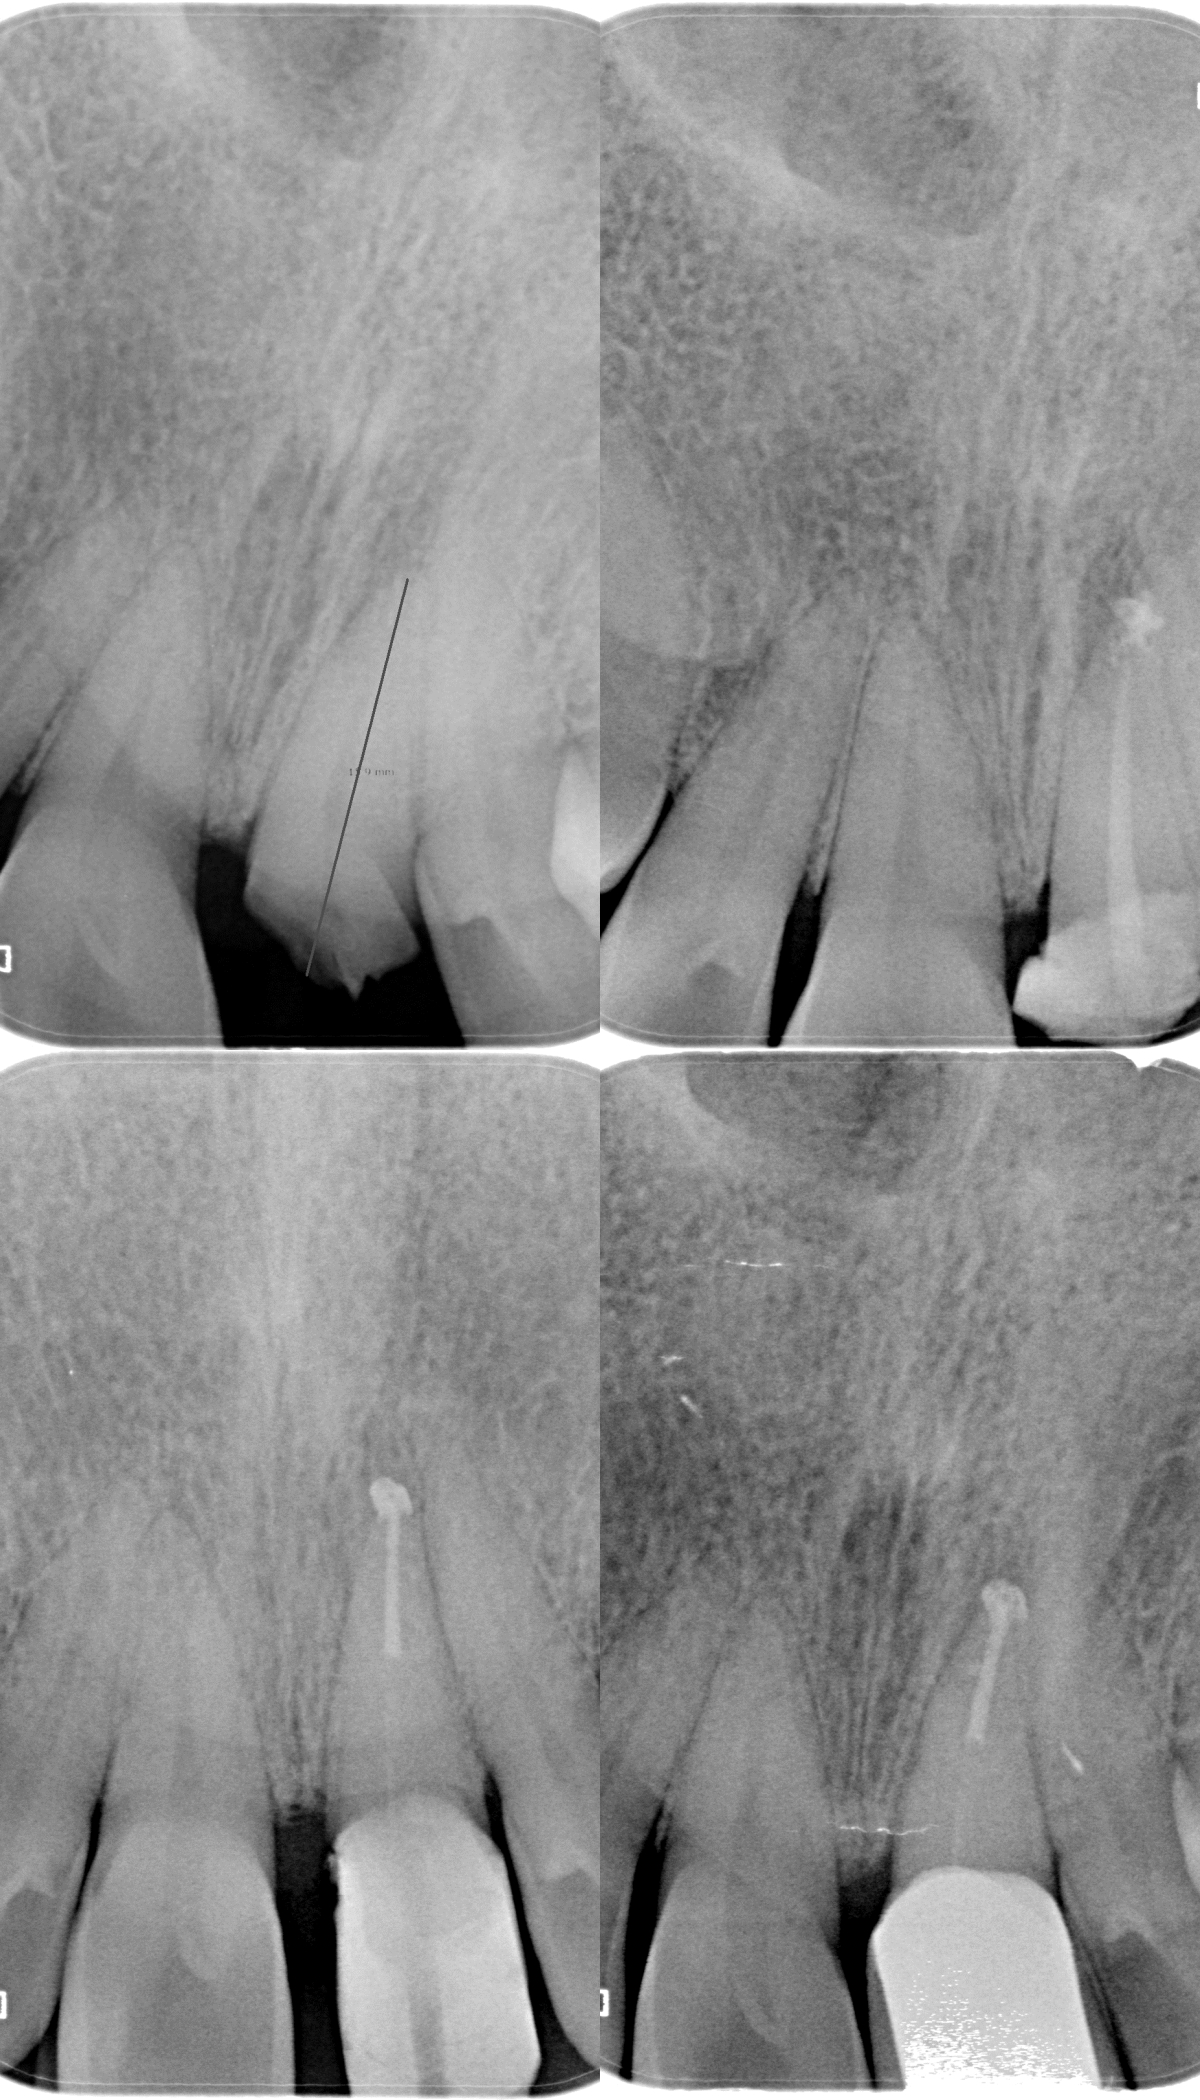

Pt 55 yoM presented with fracture of #9. History of trauma 2 wks back and was aymptomatic. Gingivectomy using electrocautery was done. Root canal therapy was completed after intermittent CAOH dressing , fibre post cemented and composite build up was done.